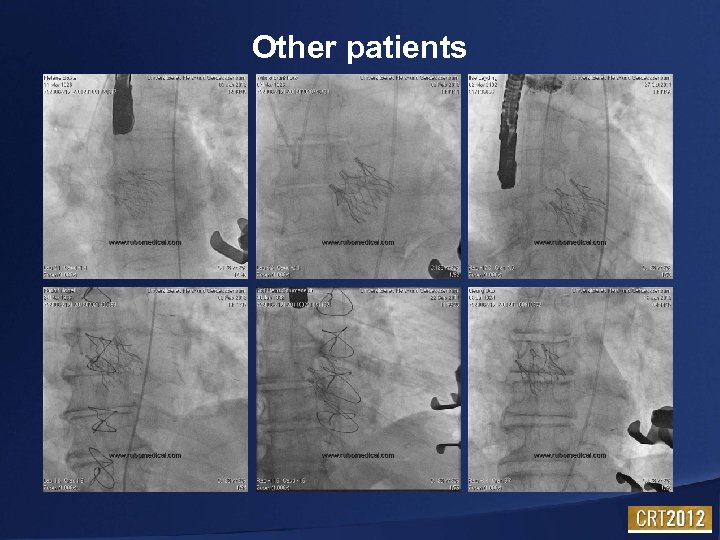

Other patients